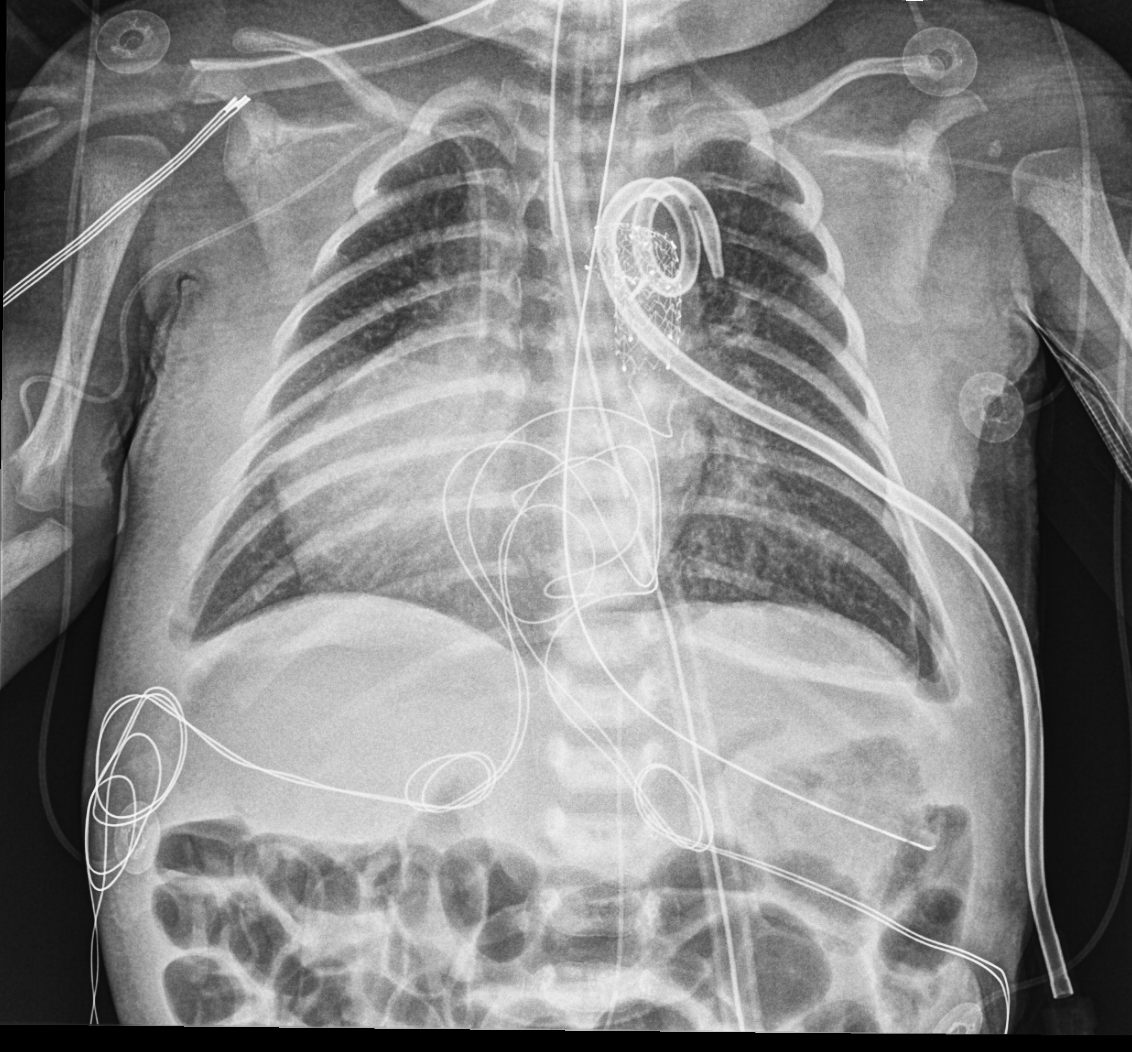

Info Images Findings Impression Reco/Acuity Case Images View Images / Launch Visage Case Notes History 2-month-old presents with decreased right arm movement, increased fussiness, and increased sleepiness for 2 days. Suspected non-accidental trauma. Exam Skeletal survey Prior Study none Dicom View Reference Material

Section 1 Submit Findings CB1550 Findings Skeletal Survey - Technique Check Skull AP/Lat Yes No Cervical and Thoracolumbar spine Yes No Chest X-Ray Yes No Ribs – Left/Right Oblique Yes No Abdominal X-Ray Yes No Pelvis with both hips Yes No Bilateral Humerus, Forearm, Hand Yes No Bilateral Femur, Tibia/fibula, feet Yes No Any additional lateral views of the extremities Yes No The exam is over or under penetrated. Yes No The exam may or may not be limited by overlying structures or soft tissues, body habitus, patient positioning, support devices, or motion. Yes No The area of concern is indicated by the patient, technologist, or care provider. Yes No The area of concern is included on the exam. Yes No Soft Tissues There is soft tissue swelling, indistinctness of fat/muscle planes, gas, or laceration in the area of clinical concern. Yes No There is an effusion, fat pad displacement, or fat fluid level. Yes No There is a radiodense or lucent foreign body. Yes No There are other densities, calcifications, post-surgical changes, or support devices in the soft tissues. Yes No Any support lines/tubes. Yes No Bone There is a break or interruption of the continuity of the cortical or cancellous bone. Yes No There is overriding of the trabeculae with apparent sclerosis. Yes No There is displacement of a fracture fragment. Yes No There is bowing of the bone in addition to the fracture at the apex of the bowed bone concerning for the greenstick. Yes No There is a spiral fracture of the leg concerning for toddler’s fracture. Yes No There is abnormal angulation or bulging of the cortical surface relative to the normal cortex which could be from a buckle or torus fracture. Yes No There is a displaced fragment which may be from avulsion by a tendon, ligament, or joint capsule or from a comminuted or other fracture. Yes No The stress trabeculae or other trabeculae of the cancellous bone are interrupted or otherwise abnormal. Yes No There is subperiosteal or endosteal reaction which could indicate a healing or subacute fracture or other abnormality. Yes No There is hard/soft callus formation. Yes No There is remodeling of the bone. Yes No There is a corner fracture or metaphyseal lesion that could be from nonaccidental trauma. Yes No There are multiple fractures of different ages. Yes No There are vertebral body/spinous process fractures. Yes No There are rib fractures. Location - posterior or lateral. Yes No There is scapular/sternal fracture. Yes No There are fractures of the digits. Yes No There are wormian bones. Yes No There are intrasutural bones. Yes No There is metaphyseal abnormality (lucencies, increased density, erosion) which may be from something other than injury such as stress, metabolic disease (e.g. rickets with loss or distortion of the zone of the provisional calcification), neoplasm (e.g. leukemia), heavy metals, inflammation, or infection. Yes No There are metaphyseal spurs. Yes No There are bony deformities involving multiple bones. Yes No The bones are gracile. Yes No There are non-healing fractures. Yes No There is/are focal or multifocal lytic/lucent, blastic/sclerotic or mixed density lesion(s) or other abnormality. Yes No Overall bone density is increased or decreased with or without thinning or thickening of the cortical or cancellous bone. Yes No Growth plates, ossification centers, apophyses The growth plate(s) is/are abnormal. Yes No There is widening of the physis from a fracture with or without displacement of the epiphysis (Salter-Harris I). Yes No There is a fracture through the physis which then extends into the metaphysis with or without angulation or displacement (S-H II). Yes No There is a fracture through the physis which then extends into the epiphysis and is intra-articular, with or without angulation or displacement (S-H III). Yes No There is a fracture through the metaphysis, physis, and epiphysis which extends into the joint space with or without angulation or displacement (S-H IV). Yes No There is narrowing of the physis from a compression fracture (S-H V). Yes No The apophysis, epicondyle, secondary ossification center, or accessory ossicle is displaced or otherwise abnormal. Yes No The ossification centers are underdeveloped. Yes No Joints and alignment There is an effusion, fat pad displacement, or fat fluid level. Yes No The epiphysis or subchondral bone is fractured, interrupted, flattened, compressed, impacted, displaced, or otherwise abnormal. Yes No There is an intra-articular loose body or chondrocalcinosis. Yes No The joint is widened, narrowed, dislocated, malaligned, or incongruent. Yes No There is pseudoarthrosis. Yes No Other findings There are developmental changes or other anatomic variants or other existing conditions that may or may not be contributing to symptoms which can or should be further evaluated non-emergently or are otherwise incidental. Yes No The remainder of the exam is abnormal for age. Yes No The lungs show focal airspace opacity. Yes No There is pneumothorax. Yes No There is organomegaly. Yes No There is intra-abdominal calcification. Yes No There is displacement of the bowel loops. Yes No There is free intraperitoneal air. Yes No The bowel loops are dilated/obstructed. Yes No There is paraspinal soft tissue abnormality. Yes No